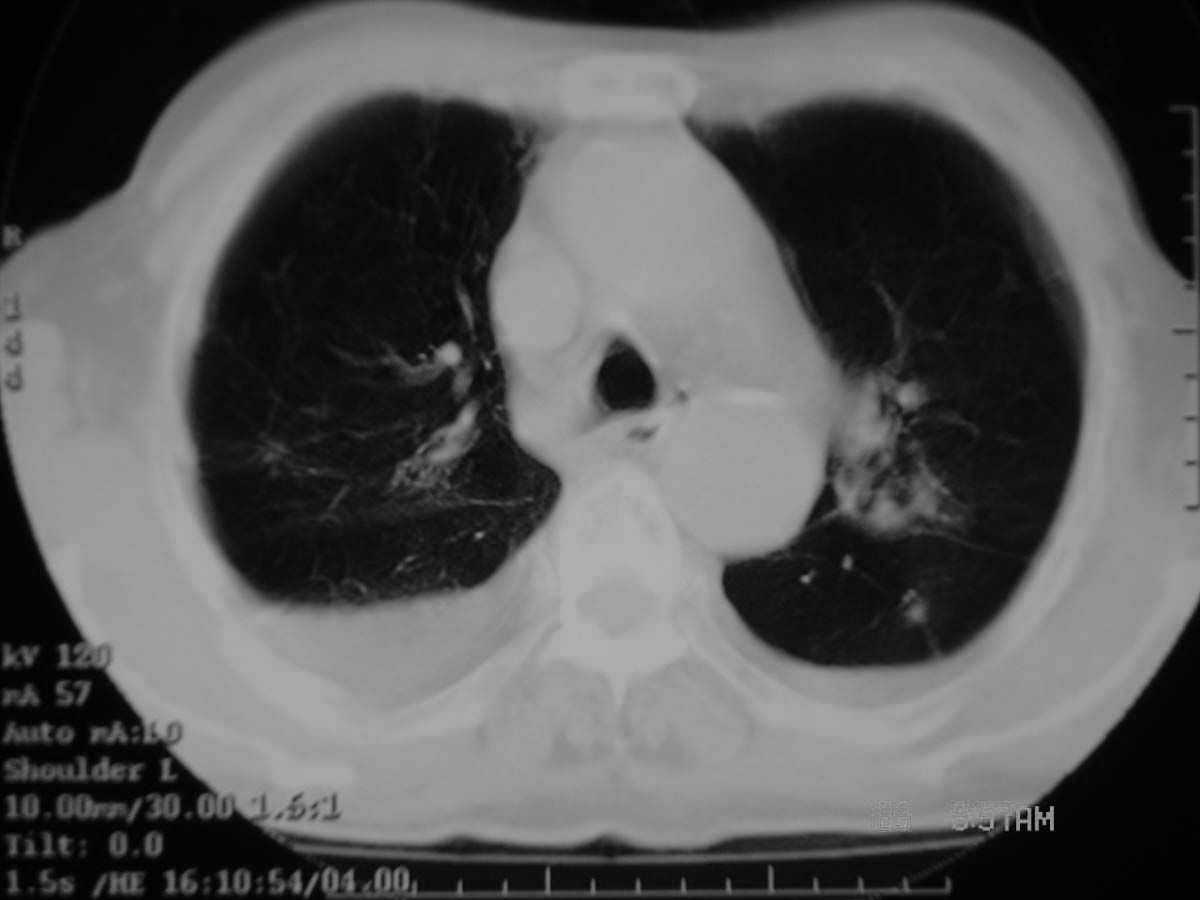

以下是引用守望可可西里在2006-11-23 14:33:00的发言:[br][br] 糖尿病病人很容易继发结核,病人又有双侧胸膜增厚、粘连、胸腔积液以及双上肺的斑片状、条索状影结核病灶影,以一元论考虑,右下肺病变首先考虑干酪性肺炎,可以正规抗炎治疗后复查,排除一般的肺炎。